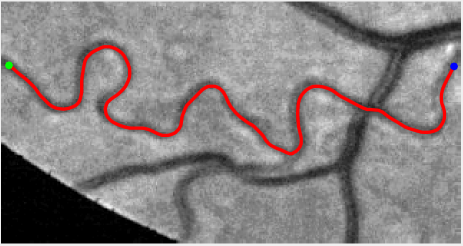

In this paper, we propose a coherence-penalized minimal path model, where the associated minimal paths favour to pass by a vessel that is located in the flatten region of an external feature map. We observe that along a piece of retinal vessel, the values of gray levels vary slowly. More specifically, retinal arteries have lower contrast of gray levels than veins due to the blood materials and imaging modality. In other words, in some extent the arteries and veins are distinguishable in terms of vesselness values. Such an observation can be used to solve the short branches problem that the minimal paths associated to a metric may pass through segments belonging to different vessels as shown in Figs. 1b and 1c. Fig. 1d shows the result from the proposed method, which can avoid such problem. Fig. 1a gives the artery-vein (AV) groundtruth. In this paper, we denote by blue and green dots the source and end points respectively.

Compare to existing minimal path models. The Riemannian metrics used in [1, 4, 5] are based on the local pointwise information. The curvature-penalized metric [7, 6] and the proposed coherence-penalized metric are able to consider more constraints, i.e., the rigidity for [7, 6] and feature coherence for our metric. These constraints are beneficial to the respective geodesics to reduce the risk of short branches combination problem. Compared to the curvature-penalized metric, our method can be more flexible since the feature map can be produced dependently on the task. In retinal imaging, veins and arteries are distinguishable in terms of gray levels or vesselness values, satisfying the formulation of the proposed model. Especially for vessels with strong tortuosity, the curvature-penalized metric, which favours a smooth curve, fails to catch the expected vessels as shown in the left column of Fig. 2. From the right column of Fig. 2, one can see that our model can obtain a good result.